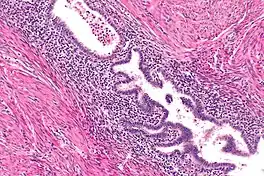

Rokitansky-Aschoff Sinus, Gallbladder Adenomyomatosis

Adenomyomatosis is frequently associated with gallstones and is often diagnosed incidentally, either from a cholecystectomy specimen or autopsy.[4][5][6] No serologic test exists to specify adenomyomatosis and laboratory studies are often normal. Co-existing diseases like cholecystitis may result in abnormal test results, such as elevated levels of white blood cells (leukocytosis), liver enzymes (transaminitis), or bilirubin (hyperbilirubinemia).[5]

Ultrasound is the preferred initial diagnostic choice for suspected gallbladder disease. Several distinct features of adenomyomatosis are discernable using ultrasound, making it a reliable modality for diagnosis.[4][5][6] The most characteristic features seen on ultrasound are the Rokitansky-Aschoff sinuses, which present either as echogenic foci when filled with biliary sludge/gallstones or anechogenic foci when filled with normal bile.[4][5][6] Other key features that may be seen include wall thickening and ring-down artifacts known as "comet tails" (produced by reverberations of sound between the sinuses).[4][5][6] Ultrasound can also distinguish between diffuse, segmental, and localized variants of adenomyomatosis based on morphology.[5][6]

In some cases, gallbladder wall thickening may be seen on ultrasound but is poorly defined and lacking specificity, particularly if the characteristic Rokitansky-Aschoff sinuses are not visualized. This can make it difficult to distinguish adenomyomatosis from other conditions that result in gallbladder wall thickening such as gallbladder cancer.[4][5][6] In these cases, MRI can prove helpful in providing the resolution needed for diagnosis. Especially effective is the T2-weighted MRI at visualizing the pathognomonic Rokitansky-Aschoff sinuses, which appear as round-shaped hyperintense cystic spaces that align in a curvilinear fashion along the gallbladder wall in a pattern described as the ”pearl necklace sign”.[4][5][6]